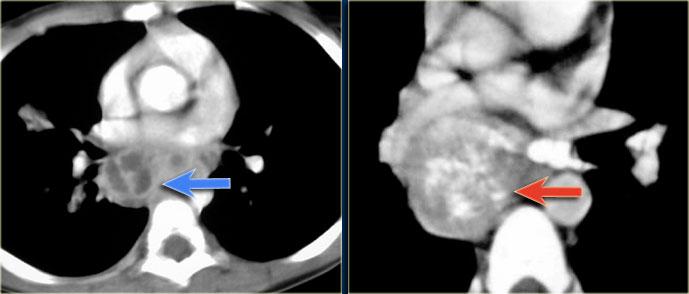

U nguyên bào thần kinh

U nguyên bào thần kinh thường có hình thoi, tỷ trọng mô mềm; 50% các khối u lồng ngực có vôi hóa.

U nguyên bào thần kinh phát triển qua nhiều khoang liên sườn và thường xâm lấn ống sống.

Các hình ảnh CT cho thấy một khối vôi hóa ở trung thất sau trải dài qua nhiều đốt sống, xâm lấn vào ống sống.

Trên các hình ảnh MRI, sự xâm lấn vào ống sống được thể hiện rõ hơn (các mũi tên).